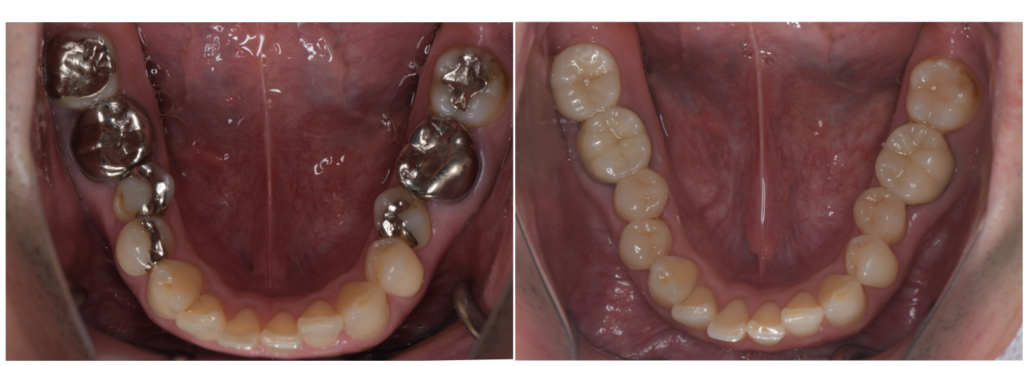

奥歯は見えにくいと思われがちですが、笑ったときや会話中、意外と人目に触れています。セラミックは天然の歯に近い色調や透明感を再現できるため、治療跡が目立ちません。

銀歯の場合、口を開けた瞬間に金属が見えてしまい、気になってしまう方も少なくありません。奥歯 セラミック 治療を選ぶことで、見た目へのストレスが減り、自然な笑顔に自信を持てるようになります。